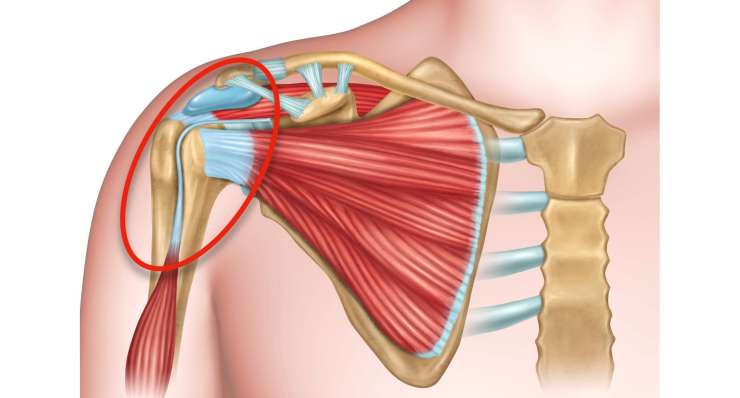

повреждение вращательной манжеты

Повреждение вращательной манжеты приводит к боли и потере функциональности плеча. В зависимости от результатов обследования, профессор, доктор медицины Франк Мартешлегер лечит это заболевание консервативным методом или с помощью артроскопии, проводя точную реконструкцию сухожилий.